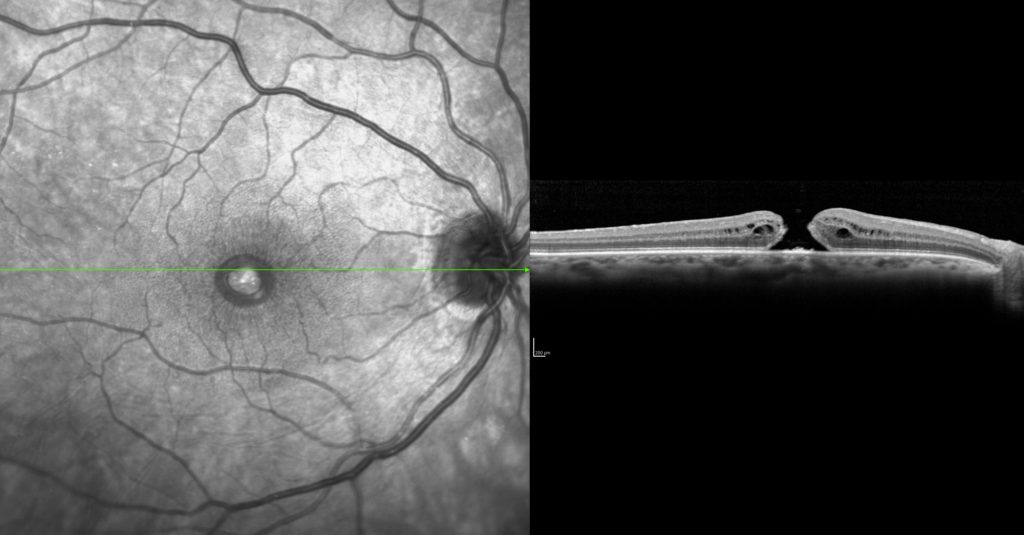

O diagnóstico é feito através do mapeamento da retina (fundo de olho) e da tomografia da retina (OCT).

Tomografia da retina (OCT) evidenciando o buraco de mácula